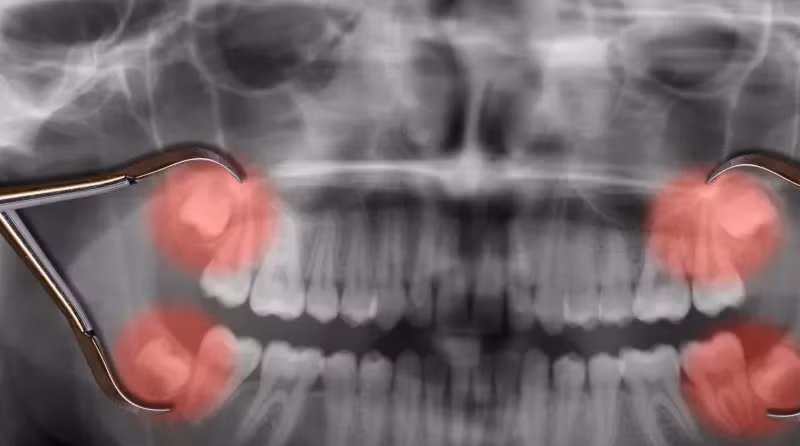

Câu trả lời nằm ở sự phát triển của cơ thể lúc còn là trẻ con. Hàm của đứa trẻ không đủ rộng để răng khôn mọc lên. Khi lớn lên, hàm của chúng cũng phát triển và có nhiều chỗ hơn cho răng khôn mọc lên. Tuy nhiên, hàm của phần lớn con người hiện đại phát triển không đủ rộng để răng khôn mọc lên dễ dàng, đó là lý do tại sao việc nhổ bỏ răng khôn trở nên rất phổ biến.

Ngày nay, các nha sĩ thường nhổ bỏ những chiếc răng khôn vì sự trồi lên của chúng có thể gây ra cảm giác đau đớn ở nhiều người. Ngay cả khi việc mọc răng khôn không gây đau, nhổ răng khôn ở tuổi thanh niên có thể ngăn ngừa các vấn đề sức khỏe sau này trong cuộc sống, chẳng hạn như nhiễm trùng nướu.

Các nha sĩ và bác sĩ phẫu thuật răng miệng thường không thực hiện nhổ bỏ răng khôn ở những người đã vượt qua tuổi 27 vì nguy cơ biến chứng, chẳng hạn như làm tổn thương tới các dây thần kinh lân cận, tăng lên.

Tuy nhiên, việc giữ lại răng khôn có thể dẫn đến các vấn đề sau này. Không phải tất cả các răng khôn đều mọc xuyên qua nướu trong giai đoạn cuối của thanh thiếu niên và đầu những năm 20 tuổi.

Khi một người già đi và nướu của họ bị tụt lại, răng khôn của họ có thể nhú ra. Trong trường hợp này, răng khôn chỉ chui qua một phần nướu nên dễ bị sâu và do đó cần phải được nhổ bỏ.